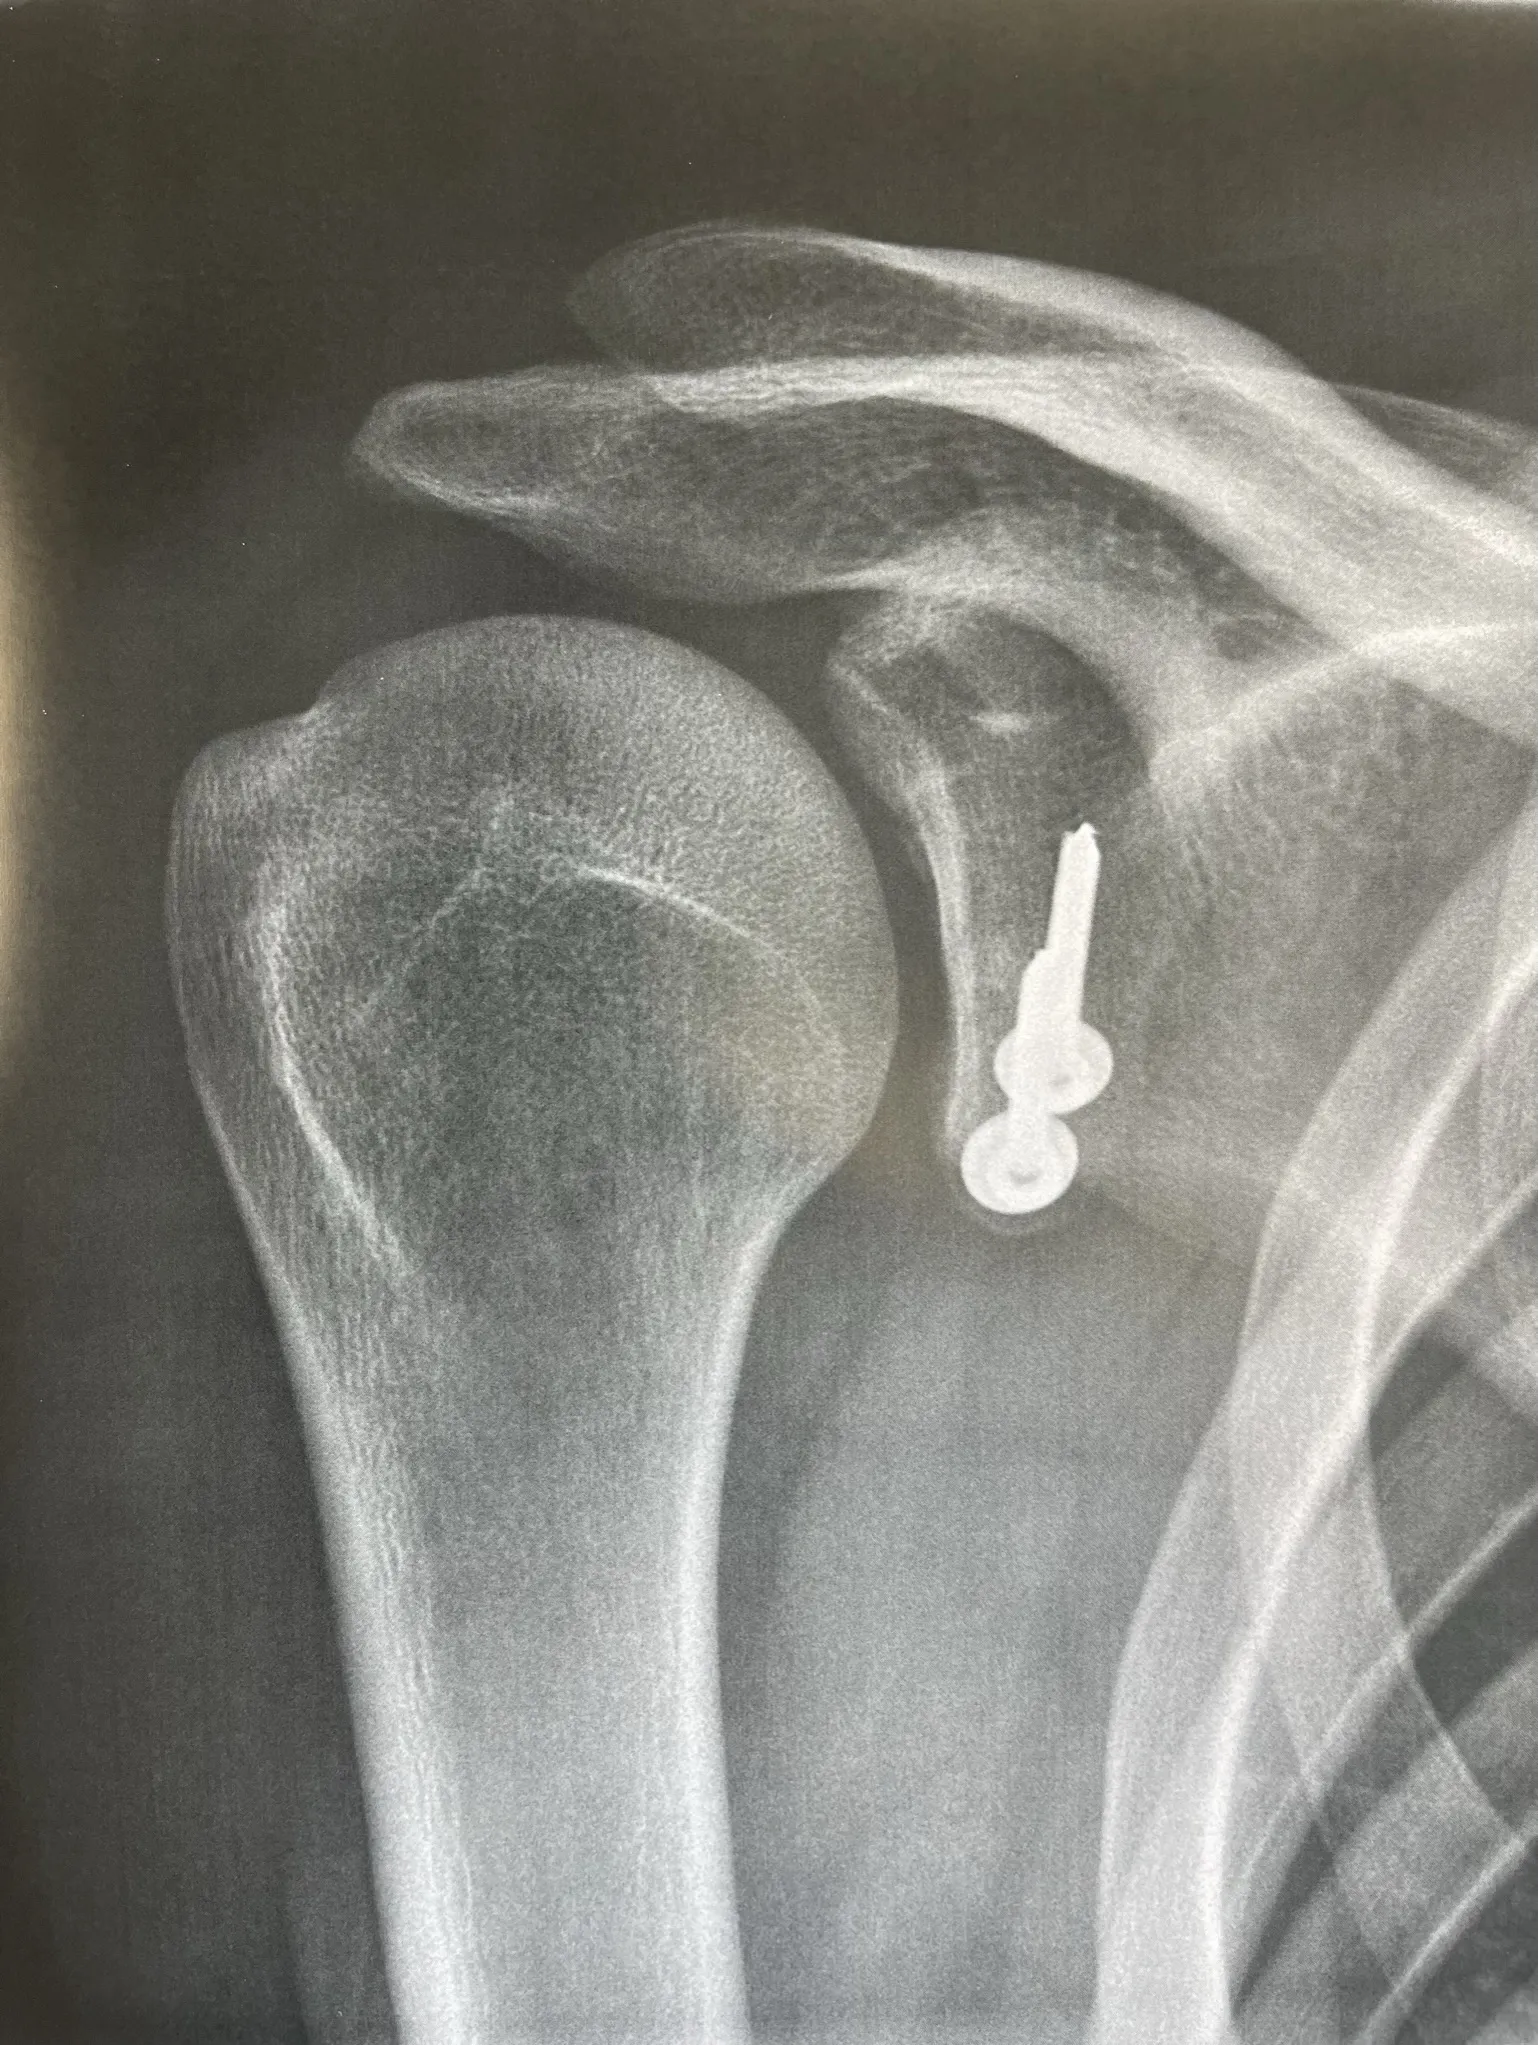

- Radiographies — bilan de débrouillage, recherche de lésions osseuses associées

Réparation de Bankart — sous arthroscopie

Pour qui ? Instabilité antérieure sans perte osseuse glénoïdienne significative (score ISIS ≤ 3).

Comment ? L'intervention est réalisée entièrement sous arthroscopie (vidéochirurgie), par 2 à 3 incisions de quelques millimètres seulement. Le labrum arraché est réinséré sur la glène à l'aide d'ancres résorbables sur lesquelles sont fixés des fils très résistants. Les ligaments gléno-huméraux distendus sont retendus dans le même temps opératoire.

Résultat : taux de succès élevé dans les indications bien posées. Reprise sport sans contact vers 4 mois. Non indiqué en première intention pour les sports de contact ou d'armé-contré.